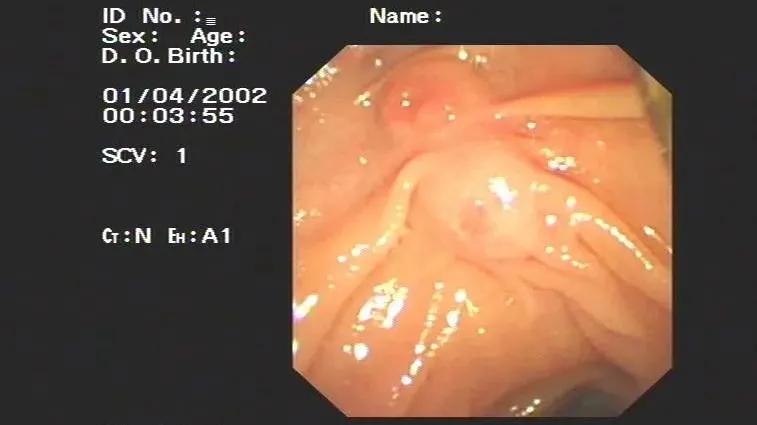

近日,江苏巴城一青年女性,因发作性上腹痛4天,去了巴中市中心医院外科进行治疗,腹部彩超显示是“胆道蛔虫”,经过消化内科主任医师会诊后,诊断胆道蛔虫明确。

之后,医生在女子口服驱虫药物治疗2天后,通过ERCP+胆道蛔虫取出术,取出一长约12cm活体蛔虫。